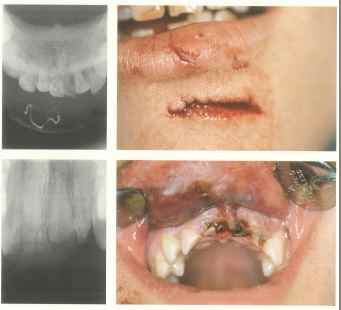

Hier sind verschiedene Probleme

zu sehen, die bei einer Langzeitfahrt Komplikationen erwarten lassen. Diese

sollten vor der Reise abgeklärt und behoben werden. Wir gehen in unserer

Praxisklinik solch einen Fall in Narkose an, sodass nach ca. 8 Tagen die

Wundheilung in den meisten Fällen komplikationslos sich selbst überlassen

werden kann.

Im rechten Unterkiefer

liegt eine deutliche Schwellung, die durch eine Eiteransammlung in diesem Gebiet zustande kommt, ausgehend von dem Wurzelrest. Hier ist eine Inzision(Schnitt) im Notfall auch von einem angeleiteten Laien in Lokalanästhesie möglich.

Hier liegt dieselbe Situation im Oberkiefer vor, die auf ähnliche Weise anzugehen ist, wie

im oberen Bild.

Ein

Unfall: Zwei Verletzungen der Weichteile mit Zahntrauma. Eine solche Wunde sollte auf jeden Fall wenigstens durch Situationsnähte so versorgt werden, dass die Wundränder adaptiert sind. Sollten die Zähne frakturiert sein, müssten sie evtl. entfernt werden. Die Wundränder sind sowohl von außen wie von innen zu adaptieren. Dies kann leicht in Lokalanästhesie (leichte Technik) geschehen.